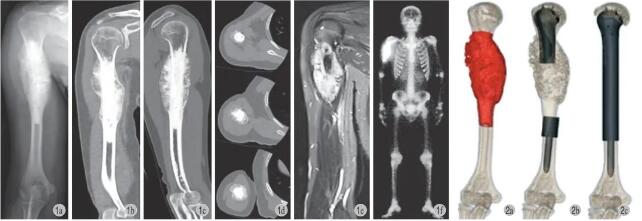

本研究共纳入 13 例,男 9 例,女 4 例,年龄16~30 岁,平均 (20.2±3.8) 岁。所有患者都接受了 X 线、肱骨 CT 三维扫描、胸部 CT 薄层扫描、上肢上臂 MRI 以及全身骨扫描或正电子发射断层扫描等术前影像学评估 (图 1)。所有患者均进行了术前活检明确病理诊断,手术分期采用 Enneking 系统分期 [27],参照 Kumta 等 [28] 提出的骨骺板与肿瘤相对位置进行分类,并按照 NCCN 的骨肿瘤指南,对高等级肉瘤患者进行新辅助化疗 (表 1)。

图1 例 1,男,19 岁,右侧肱骨近端硬化性骨肉瘤 a~d:术前 X 线、三维 CT 显示肿瘤侵犯右肱骨近端;e:术前 MRI 示右肱骨远端骨质破坏伴软组织包块;f:术前 SPECT 显示右肱骨近端核素浓集